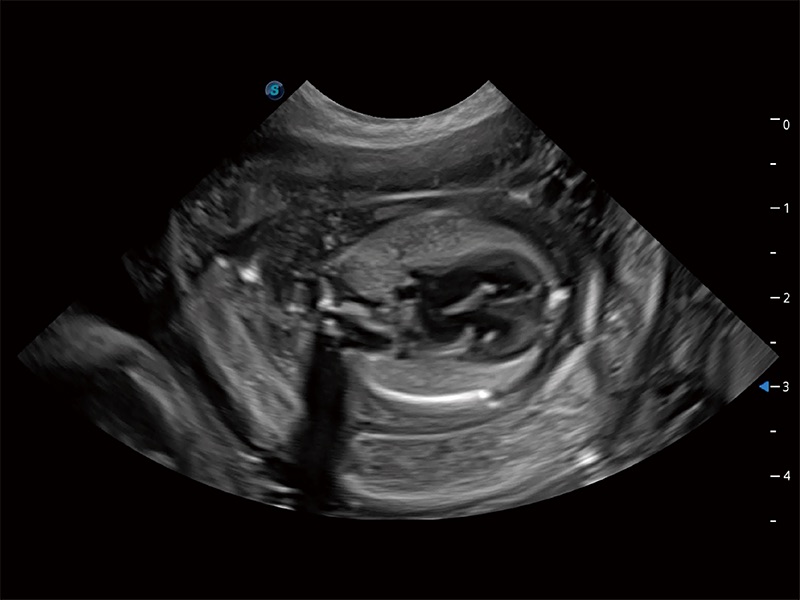

ProPet 80 配备了丰富的心脏探头群、先进的成像技术和专业的心脏测量工具,可帮助动物医生为不同体型和生理结构的动物提供心脏和心肌功能的全面评估。

ProPet 80 专为动物医生设计,对不同的动物体型和生理结构作出了针对性的优化。通过动物影像专用软件,可满足个性化的应用需求,帮助动物医生获得更精确的诊断数据。

提供解剖示意图、标准超声图像、扫查手法涂和操作者实时检查图像,指导操作者进行标准切面的正确扫查。